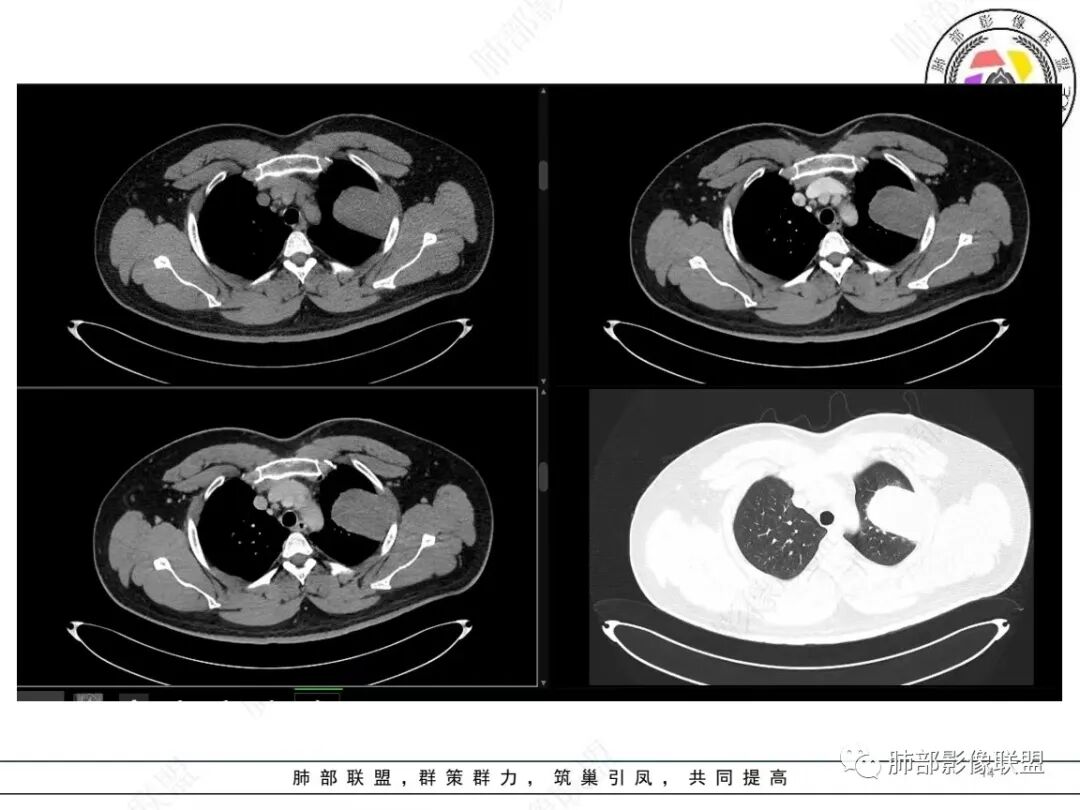

青年男性,咯血;CT示左肺上叶胸膜下软组织肿块,边界尚清,宽基底与胸膜相连,增强动脉期内见细条状血管影,轻度延迟强化,定位:肺外,胸膜外脂肪存在,考虑脏层胸膜起源;定性:考虑SFT。

影像表现:左肺上叶占位合并出血,胸膜栽赃,边缘强化,局部见血管影,中心密度20Hu,无强化,符合非液化坏死。定位:肺内,定性恶性(明显血管影,栽赃排除错构瘤,中心无强化排除PSP,无明显清楚的坏死边界,强化不符合肉芽肿,排除结核),年龄轻,无长时间吸烟史和肺气肿改变,肉瘤样癌可能性很小,与支气管无确切关系,所以病理类型考虑来源于肺间叶组织的肉瘤,骨外尤文?滑膜肉瘤?

有血供,强化不明显,周围肺出血,肺组织受压改变,定位肺外,胸膜增厚,部分胸膜下脂肪间隙存在,不确定肋骨是否受侵犯,部分层面与肺动脉分界不清,感觉推移,如果供血要考虑sft,强化不符合,有血管进入,但是强化不明显,密度相对均匀,所以不考虑坏死,富含粘液可能,咯血,说明累及支气管了,有一定侵袭性,肿块大,考虑间叶来源肿瘤,与胸膜接触面相对不是宽基底,综合考虑滑膜肉瘤可能,典型的滑膜肉瘤一般铺路石改变,这个又觉得信号相对均匀了一些学习中

定位肺内明确,来源间叶组织明确,年龄和吸烟史情况排除肉瘤样癌,剩下的就基本上只有骨外尤文和滑膜肉瘤了,再加上强化低,骨外尤文就肯定首先考虑。